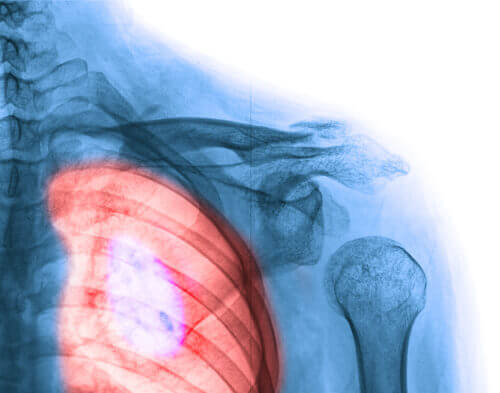

1. Brystkreft

Brystkreft har, uten tvil, størst innvirkning på kvinner. Imidlertid bør vi nevne noe viktig her: Den har også høyest overlevelse.

Du kjenner sikkert noen i din omgangskrets som har brystkreft, eller kanskje du selv har mistet en du er glad i til denne forferdelige sykdommen. Men det er vitenskapelige fremskritt hver dag: Flere og flere kvinner overlever brystkreft. Å kjenne på brystene dine selv, og mammografi, er nøkkelfaktorer for å oppdage brystkreft tidlig. Her er noen tegn og symptomer du bør huske på: